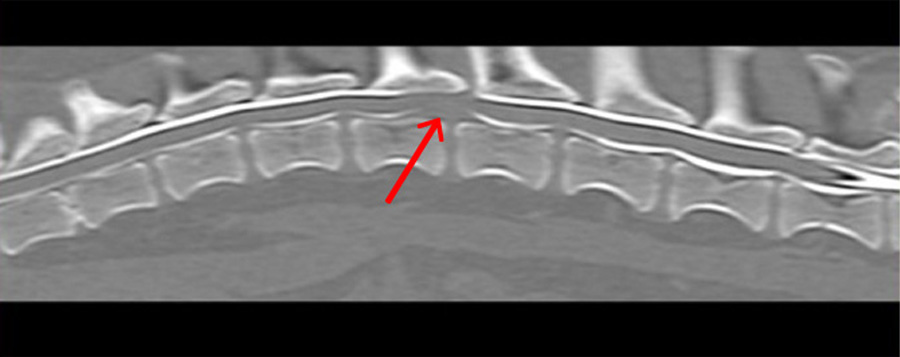

脊髄造影CT検査

椎間板ヘルニアに対する手術に対して、脊髄造影CT検査を行い、画像専任の獣医師による読影を行った後に正確な場所とヘルニアの状況を確認し、手術を実施しています。